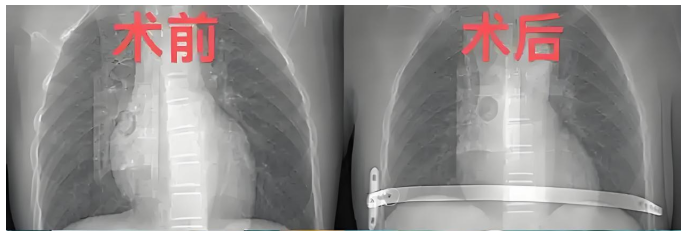

经过充分的术前准备与风险评估,胸外科团队为小文实施漏斗胸矫正手术。手术核心在于通过精准植入矫正钢板,逐步重塑胸廓正常形态,解除对胸腔脏器的压迫。团队凭借丰富的临床经验和娴熟的操作技巧,在保障安全的前提下,精准完成钢板植入操作,最大程度还原胸廓生理结构。

2025年12月8日,小文再次来到我院,胸外科团队为其实施钢板取出手术。当看到检查报告上“胸廓形态正常、各项指标达标”的结论时,小文和家人脸上露出了久违的灿烂笑容。如今的小文,身姿挺拔、活力满满,彻底摆脱了疾病的束缚,正以崭新的面貌迎接学习与生活的新挑战。